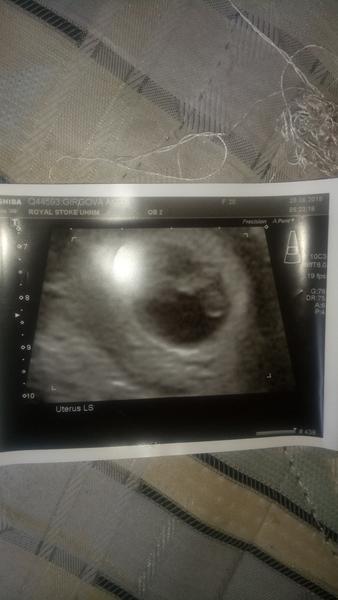

dnes som bola na sono 1 krát podla poslednej menštruácie som mala byt v 8 tyzni a podla sona som v 5.Problém je vtom že lekár povedal že som v 5 tyždny ale plod vobec nevidel ☹ povedal že mám príst na kontrolné sono v pondelok.Som strašne zúfalá má stým niekto skúsenosti?

Ja som bola tento týždeň 5+6 tt a bolo vidno aj akciu srdiečka

Teraz som.v 6 tyzdni a je vidno gestacny vacok uz